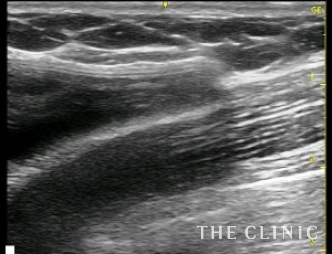

シリコンバッグ

カプセル拘縮

- シリコンバッグ

- カプセル拘縮

- 10年

- バッグエント CRF豊胸

10年前に乳腺下にバッグを挿入しています。脇の下からバッグを抜去して片胸に230㏄づつCRFを注入しました。取り出したバッグの右側はカプセル拘縮が強く変形していました。

シリコンバッグによるカプセル拘縮のエコー診断カルテ